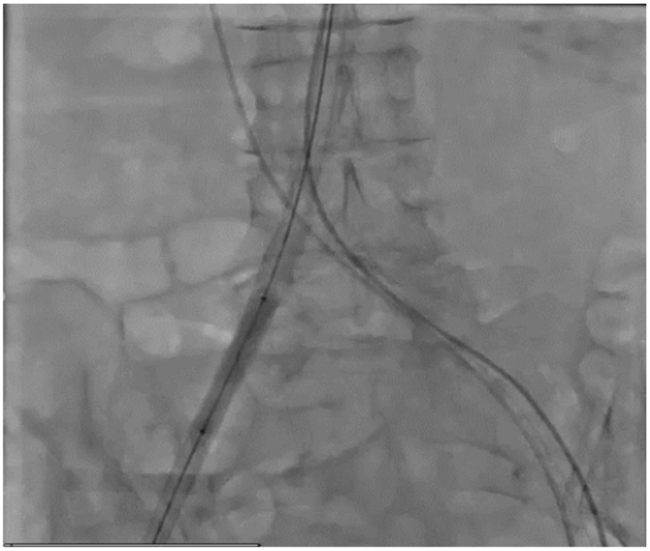

Following contralateral positioning of a crossover wire and preclosure with 2 Proglide sutures (Abbott Vascular), a 14-Fr Edwards eSheath (Edwards Lifesciences) was inserted into the descending aorta. A 7 x 40 mm Armada balloon (Abbott Vascular) was then used to further dilate the eSheath endovascularly (Figure 1). A 23-mm Sapien 3 valve (Edwards Lifesciences) was delivered through the sheath and deployed without difficulty (Video 1). Following valve deployment, the sheath was removed and hemostasis was achieved with the predeployed sutures. Final femoral angiography demonstrated hemostasis without vessel injury.